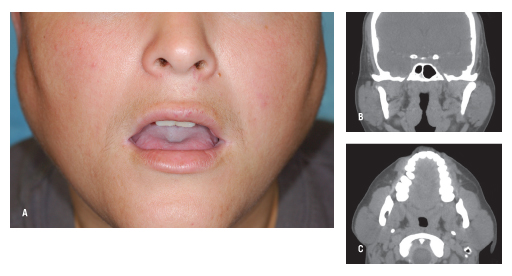

look at all these women with gigachad jaws

just bulimiamaxx bro it grows your jaw and helps you get to 3% bf